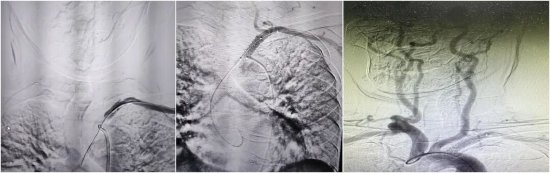

三、巅峰“会师”:双向夹击打通生命通道

所谓“会师技术”,就像是在山体隧道挖掘中,从山的两端同时动工,在中间汇合。一方面,继续保留股动脉通路,从近心端进行“正向”试探;另一方面,在张女士左侧手腕处开辟第二条微创通道(桡动脉入路),从血管远端进行“逆向”进攻。能否在原本搏动微弱的桡动脉上穿刺成功是逆向通路建立成功的关键。在神经内科介入团队的努力下,成功穿刺左侧桡动脉,在DSA高清影像的引导下,逆向导丝犹如长了眼睛一般,缓慢且坚定地向前推进。终于,在反复调整角度和路径后,两根导丝在闭塞段内精准“会师”。随后,利用逆向导丝作为“生命线”,将正向球囊顺利送至病变部位,依次进行扩张。随着一枚支架精准释放在左锁骨下动脉开口处,血管瞬间被撑开。

术后即刻造影显示:闭塞的血管重新开通,血流畅通无阻,左侧椎动脉恢复了正向供血。原本摸不到的左侧脉搏、乃至远侧桡动脉也恢复了有力跳动。